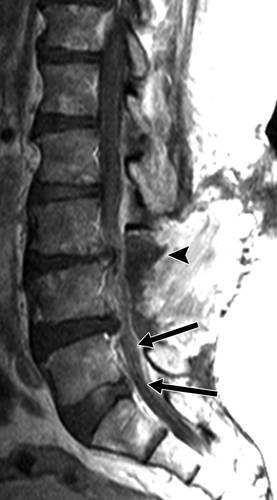

图13A-70岁的男性,在2年内进行数次腰椎手术,进行性疼痛。 骨扫描显示L2-L3间隙摄取量增加(未显示)。 血液检查显示C反应蛋白浓度和红细胞沉降率升高。矢状T2加权MR图像示出了L2-L3 椎间盘炎(箭头),合并L2-L3相邻终板和椎体破坏。 L2和L3椎体T2信号强度增高,表明水肿和梗死。